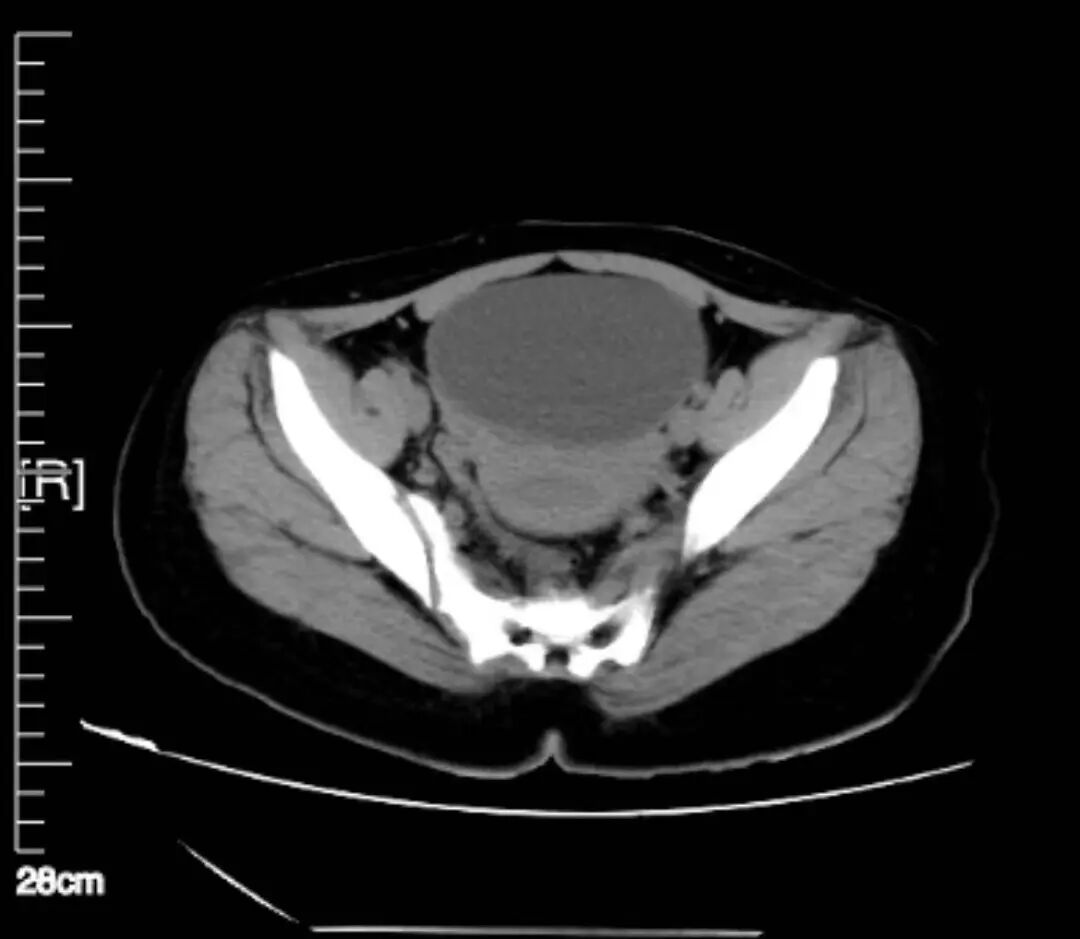

少见!卵巢囊肿蒂扭转 “您快给我女儿看看吧,这到底是怎么了?”近日,一位40多岁的母亲扶着一名十几岁的女孩走进区人民医院妇科门诊。 她的女儿小叶已被腹痛折磨了三天。但因正值初三学习重要时期,而且短时间休息后腹痛有所缓解,小叶就没有将腹痛情况告知家长及老师。 但现在她仍然感觉下腹持续性疼痛,且有阵发性加剧,才由家长带来我院就诊。坐诊的妇产科主任医师沈娟仔细询问病史并进行查体,发现小叶盆腔内可扪及一包块,直径约10cm,边界清,活动欠佳,并伴有压痛,结合中下腹部CT提示“两侧附件区见囊状低密度灶,右侧显著,大小99*58mm,内见分隔,壁局部增厚”。当即考虑卵巢囊肿蒂扭转可能,卵巢连带同侧的输卵管如同拧麻花一样扭转在了一起,扭转导致卵巢血供阻断,时间越长、缺血坏死会越严重,甚至会导致卵巢切除、感染甚至血栓形成等更大的危害,尽快手术是最好的解决办法。建议立即住院,沈主任立即开好住院手续,叮嘱一定要马上办理入院。然而当天患者及家属并末遵照医嘱办理住院,留下的联系方式也联系不上。 担心!或将失去一侧卵巢 经过多方努力,第二天中午小叶终于在她母亲的陪同下出现在了妇科病房。此时,距离最早发生腹痛己过去72小时。沈主任考虑到女孩病情的危急性,决定立即给女孩实施手术。 术前沈主任很纠结,她告诉女孩的母亲,从医学原则上来讲,一旦考虑卵巢囊肿蒂扭转,特别对于年轻患者,应尽快剖腹或腹腔镜手术探查。对于扭转部位松散或是组织坏死不明显者可先行扭转囊肿复位,若血供恢复良好可选择保留该侧正常卵巢组织的手术方式。而对于伴发组织缺血坏死者,一般情况下不允许将扭转囊肿复位,而应直接自蒂部给予切除。但小叶才13岁,花一样的年纪,若切除卵巢,将对她以后的生长发育及婚姻家庭生活造成极大的影响。 恳求!尽力保住女孩卵巢 “您一定要救救这个孩子,没了卵巢,我的孩子这辈子就完了。”母亲听后百般恳求。沈娟主任说,作为医生自己也很想保留住孩子的卵巢,但这意味着她和这个女孩都将承担一定的医学风险。因为卵巢囊肿蒂扭转导致组织血栓的形成,通过松解,有可能会出现血栓脱落并发心脑栓塞的可能,严重的甚至会威胁患者生命。心情迫切的女孩儿母亲最终也愿意和医生一起承担这种风险,并在手术知情书上签上了字。 成功!精心手术还患者健康 (右一为沈娟,正在实施手术) 沈主任给小叶实施了腹腔镜手术,术中见右侧卵巢增大形成直径约10cm囊性包块,囊壁厚,表面暗红色,右侧卵巢固有韧带、右侧输卵管峡部形成蒂部,右侧附件顺时针扭转720度,蒂部外侧输卵管至伞端水肿增粗呈暗红色。考虑己有局部坏死,卵巢是切?还是保留?切,对孩子日后的生活将会有严重影响;不切,坏死的组织会不会发生感染,甚至血栓脱落形成更严重的并发症?沈主任考虑再三,“孩子还小,先复位,等等看!” 等什么呢?等等看复位后血供能不能恢复,能恢复就还有保留的可能!时间一分一秒的过去,沈主任小心翼翼地将已经扭结在一起的卵巢输卵管逐步松开,终于看见卵巢和输卵管的颜色肉眼可见地在慢慢恢复,再小心将坏死的卵巢组织剥除,尽可能保留血供丰富的相对正常的卵巢组织及完整的输卵管,手术进行地非常顺利,手术结束后,因为孩子的情况特殊,每次交接班沈主任都会反复叮嘱值班医生和护士多留意这个孩子。 出院!卵巢功能完全恢复 五天后,女孩出院了,电话回访中得知,一个月后,这个女孩儿的例假就正常来了,术后女孩儿来院复查,得知她已经正常来例假两次,而且盆腔彩超提示子宫及双侧附件未见异常,女孩儿的卵巢功能已经完全恢复了,并且因为我院采用了腹腔镜微创手术技术,患者腹部仅有0.5-1cm的切口,几乎看不出瘢痕,也不会对花季少女的身心留下任何不良影响。 妇科专家提醒各位家长,妇科疾病并不是只发生在已婚妇女身上,很多并无性生活的女性甚至幼小的女童也有可能患病,家长平时要多观察,时刻注意孩子的体态特征变化,一旦孩子出现肚子无故变大、隆起,急性腹痛等可疑特征,还需及时就医诊断。 科室介绍 南京市溧水区人民医院妇科是一个专业技术实力雄厚、梯队化管理严谨、亚专科技术人才齐备的医学重点专科。科室坚持“以人为本,科技领先,服务第一”的宗旨,为患者提供个体化、人性化和多元化的治疗方案,营造了一个极具现代化医疗水准的女性就医环境。 科室核定床位43张,在岗医护人员近30人,高级职称4名,硕士研究生3名,硕士在读2名,南京中医药学会妇科专业委员会常务委员1名,南京医学会妇产科分会委员1名,南京医学会计划生育/生殖健康分会委员1名,江苏省妇科人工智能与微无创专业委员会委员1名,江苏省中西医结合学会外治法专业委员会青年委员1名,中国妇幼保健协会妇科内分泌专业委员会健康扶贫工作学组青年委员1名,南京医学会妇产科分会腔镜学组、肿瘤学组、内分泌学组成员各1名。 科室下设妇科肿瘤、普妇、内分泌与不孕不育、计划生育、宫颈疾病门诊以及盆底康复亚专科,拥有腹腔镜、宫腔镜、LEEP高频刀、数码电子阴道镜、聚焦超声治疗仪、超导可视人流等设备,为妇科疾病诊疗提供高质量保障,科学规范治疗子宫卵巢良恶性肿瘤、不孕症、生殖内分泌疾病、各种炎性疾病(阴道炎、宫颈炎、盆腔炎)以及计划生育等疾病。科室先后获得南京市卫生系统新技术引进三等奖、溧水区科技进步三等奖,连续多年获得医院综合目标贡献奖、医疗质量优秀奖、先进技术奖等。承担多项省市级科研项目,近五年发表医学论文数篇。 妇科专家门诊:每周四、周五,专科门诊:周一至周日。 专科特色 1.经脐、经阴道单孔腹腔镜手术 在溧水区率先开展了妇科经脐、经阴道单孔腹腔镜手术,使溧水区妇科手术进入无痕时代,广大女性同胞不出溧水即可享受到优质的技术服务。 2.宫腔镜手术 子宫内膜息肉切除术 子宫粘膜下肌瘤切除术 子宫嵌顿环取出术 输卵管插管疏通治疗不孕症。 3.盆底康复技术 生殖康复:子宫复旧/人流术后子宫复旧、盆底功能评估及康复、尿失禁、子宫脱垂、阴道紧致、慢性盆腔炎、乳腺小叶增生、乳房护理。 哺乳期乳腺全程管理:母乳喂养指导、乳汁淤积、乳腺理疗疏通、乳头问题(白斑、皲裂)、少乳、回乳护理。 形体康复:腹部塑型、臀部塑型、腿部塑型、乳房塑型、腹直肌分离、耻骨联合分离、疤痕恢复、妊娠纹淡化、产后骨盆调整、营养心理指导与干预。 4.妇科恶性肿瘤的规范化治疗 宫颈癌、子宫内膜癌、卵巢癌、子宫肉瘤等可行经腹及经腹腔镜手术。 此外,常规开展腹腔镜下子宫肌瘤剔除术、卵巢囊肿剥除术、附件切除、全子宫切除、输卵管造口术及复通术等手术。开展腹腔镜下盆腔淋巴结清扫术、腹腔镜腹直肌悬吊术治疗子宫脱垂、腹腔镜下输卵管妊娠切开取胚术等新技术。 专家介绍 沈娟 妇科主任医师。 2001年毕业于扬州大学医学院。2012年9月至2013年8月在南京医科大学第二附属医院妇产科及腔镜组进修学习。 擅长妇产科常见病、多发病和疑难危重病人的诊治,熟练进行妇科各种手术及计划生育手术,特别是妇科各种微创手术。 专家门诊时间:每周三 吴彩丽 妇科主任医师。 擅长妇科常见病、多发病和疑难重症患者的诊治,擅长妇科内分泌疾病的诊治,熟练进行各种妇科手术及计划生育手术,擅长腹腔镜、宫腔镜、阴道镜的诊治。 专家门诊时间:每周五。